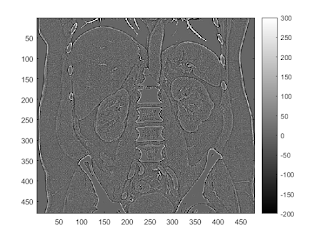

high-pass by hand

b = [-1, -1, -1; -1, 7.9866, -1; -1, -1, -1];

I2 = conv2(I,b,'same');

imagesc(I2);

colorbar

mean(I2(:))

caxis([-200,300])

ans = -0.0026